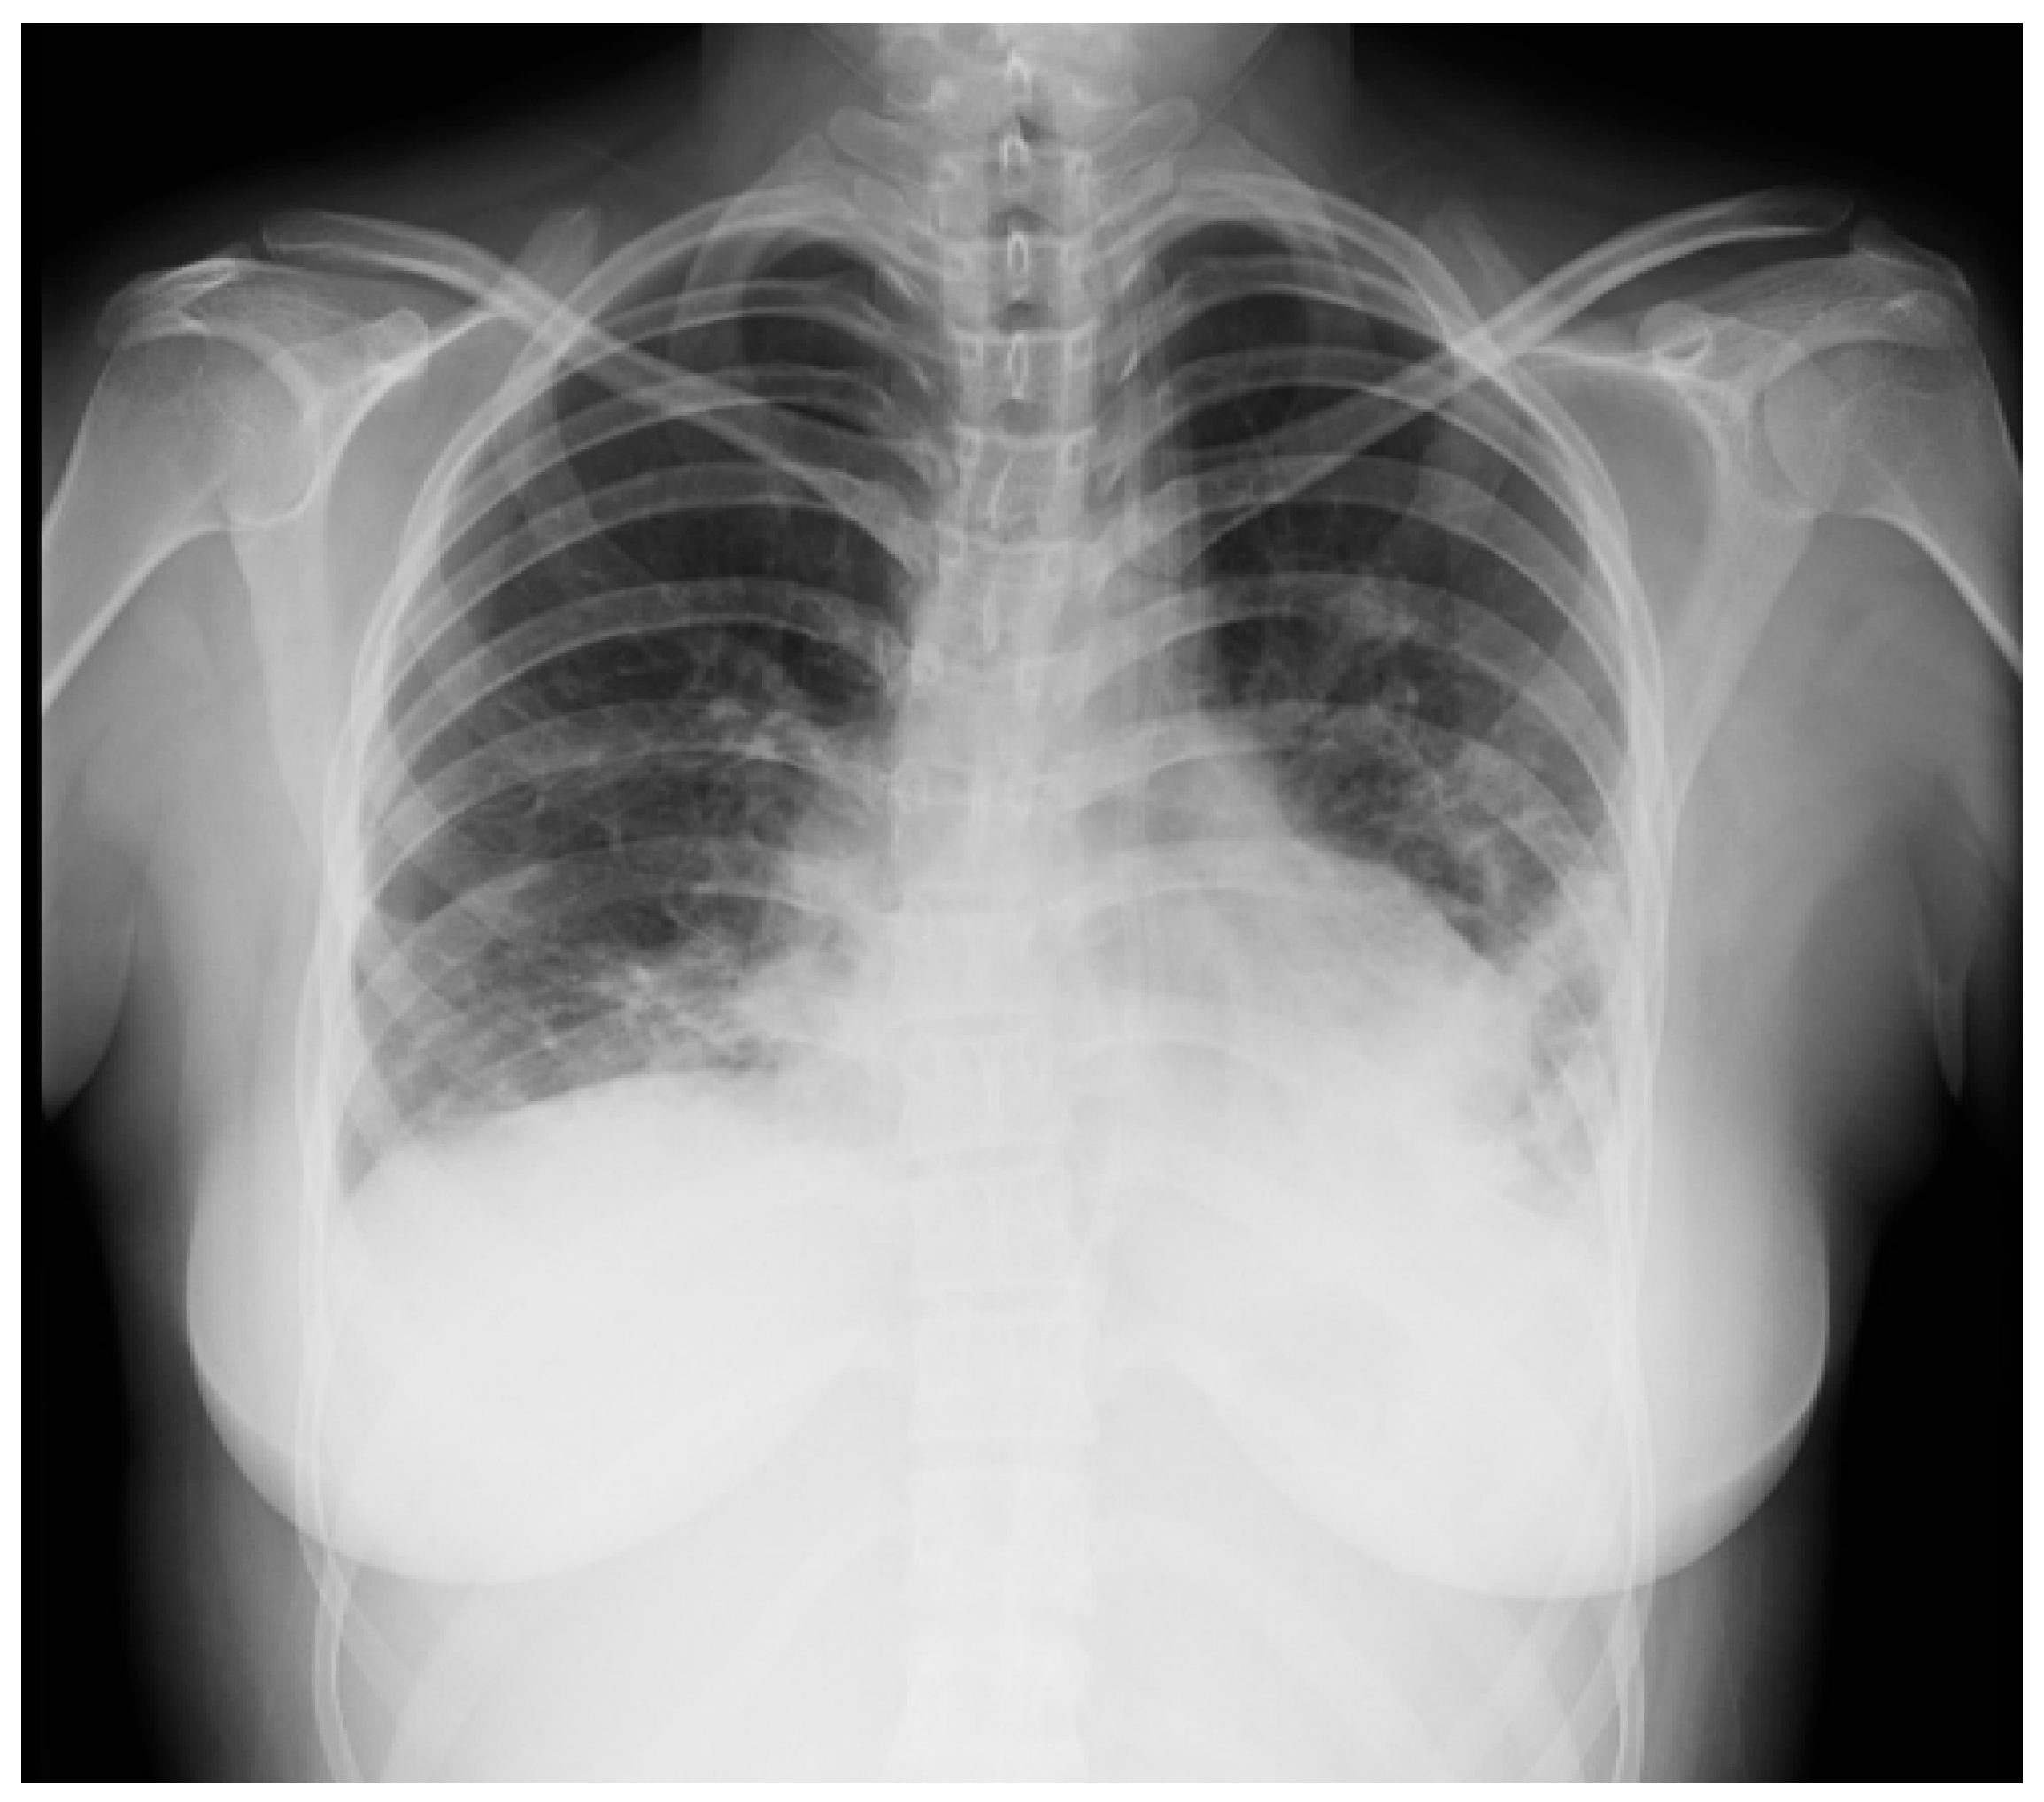

2.2. Case 2